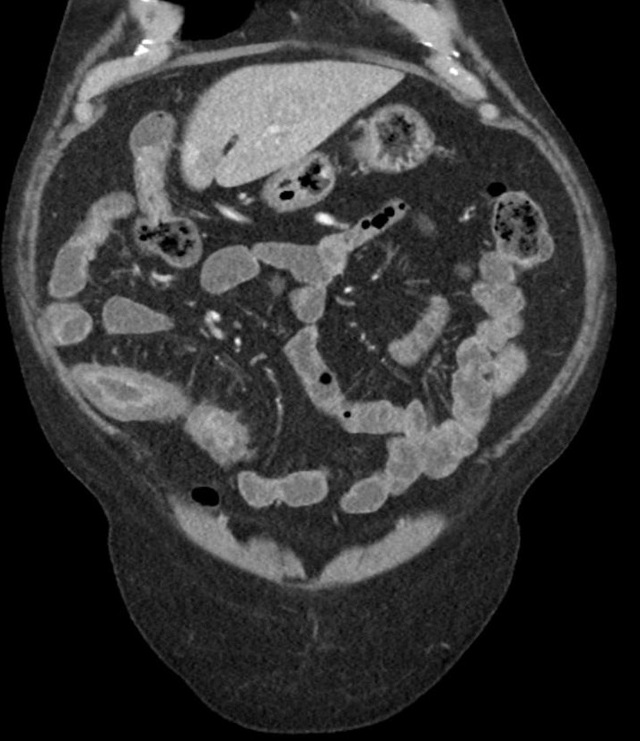

直到有一天,一位内科医生建议我进行一系列深入的检查。通过内镜检查和影像学检查,他们发现了肠道的异常炎症和穿透性病变,这些特征与克罗恩病的诊断标准高度吻合。那一刻,我的心情复杂难言,既有终于找到病因的释然,也有对未来治疗道路的担忧。

克罗恩病的诊断并非易事,它需要医生通过详细的临床症状观察、实验室检查和影像学检查来综合判断。对于我来说,这个过程是漫长而艰辛的,但也是我与。